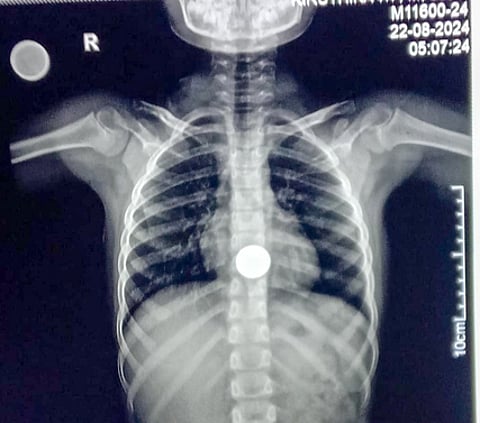

TIRUPATTUR: Doctors at the Tirupattur Government Hospital successfully removed a Rs 5 coin from the food pipe of a seven-year-old girl, Kanishree, on Sunday. The child is learnt to have swallowed the coin, which was given to her by a relative, on Friday.

In about half an hour, Dr Deepanand, along with anaesthetist Dr Sudha and Dr Velmurugan successfully carried out the procedure and removed the coin.